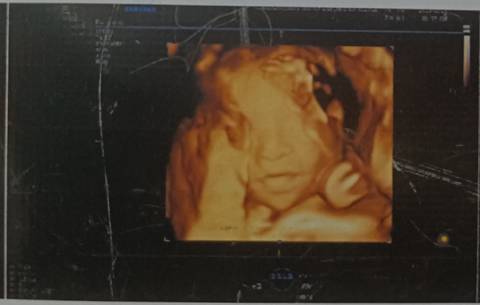

22+5终于看见宝宝脸部了,一切正常,医生说就是腿短了一点,这个最后会长吗?

这个你不用担心,你现在才22周,后面多补充优质的蛋白营养跟得上宝宝也是惠能长的。

不用担心肯定会涨上去的呀,这个时候补充钙片,多吃点含钙高的食物就可以了

其实这个也算是正常,没有什么大的问题,你平时尽量还是要多注意休息,不用太担心的哦